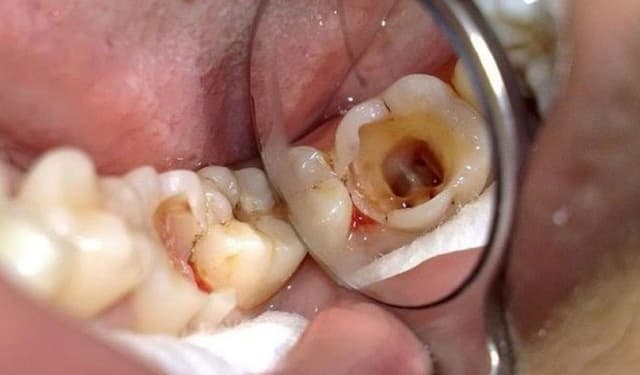

Nguyên nhân phổ biến dẫn đến đau răng do sâu răng

Đau răng do sâu răng là tình trạng rất hay gặp khi lỗ sâu tiến gần đến ngà hoặc tủy răng, khiến bạn đau nhói khi ăn đồ ngọt, chua, nóng lạnh hoặc đau âm ỉ cả ngày. Bài viết dưới đây giúp bạn hiểu rõ nguyên nhân phổ biến dẫn đến đau răng do […]